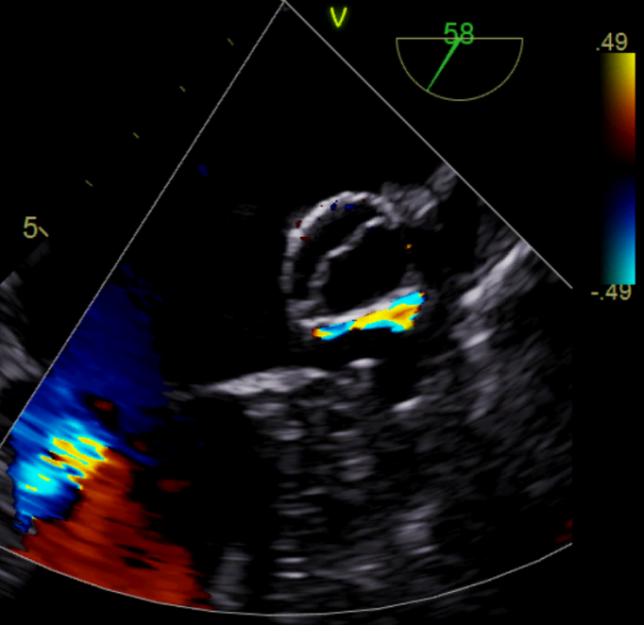

如图3所示,术中造影显示患者的左心耳固定区尺寸为23mm、深度25mm,选用规格为锚定盘直径26mm,密封盘直径 31 mm的左心耳消融封堵器植入到左心耳内。如图4-5所示,消融前后采用德诺电生理标测导管对左心耳进行电信号检测,对比结果表明左心耳电信号完全隔离;如图6所示,术者分别在左心耳消融前后进行了冠状动脉造影,造影显示回旋支无明显变化,无痉挛等不良事件发生;如图7-8所示,封堵器解脱前对左心耳消融封堵器进行了牵拉测试,器械无移位,造影及TEE超声显示左心耳完全封堵,无残余分流。

图7 左心耳封堵器牵拉测试

(a)DSA造影显示封堵良好

(b)TEE无残余分流

图8 左心耳封堵器封堵DSA和TEE影像